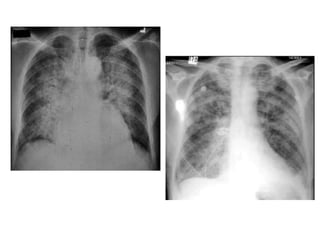

EDEMA AGUDO PULMONAR

• Se define el edema pulmonar como la presencia de líquido en los espacios extravasculares

(intersticial y alveolar) del pulmón en cantidad superior a la fisiológica.